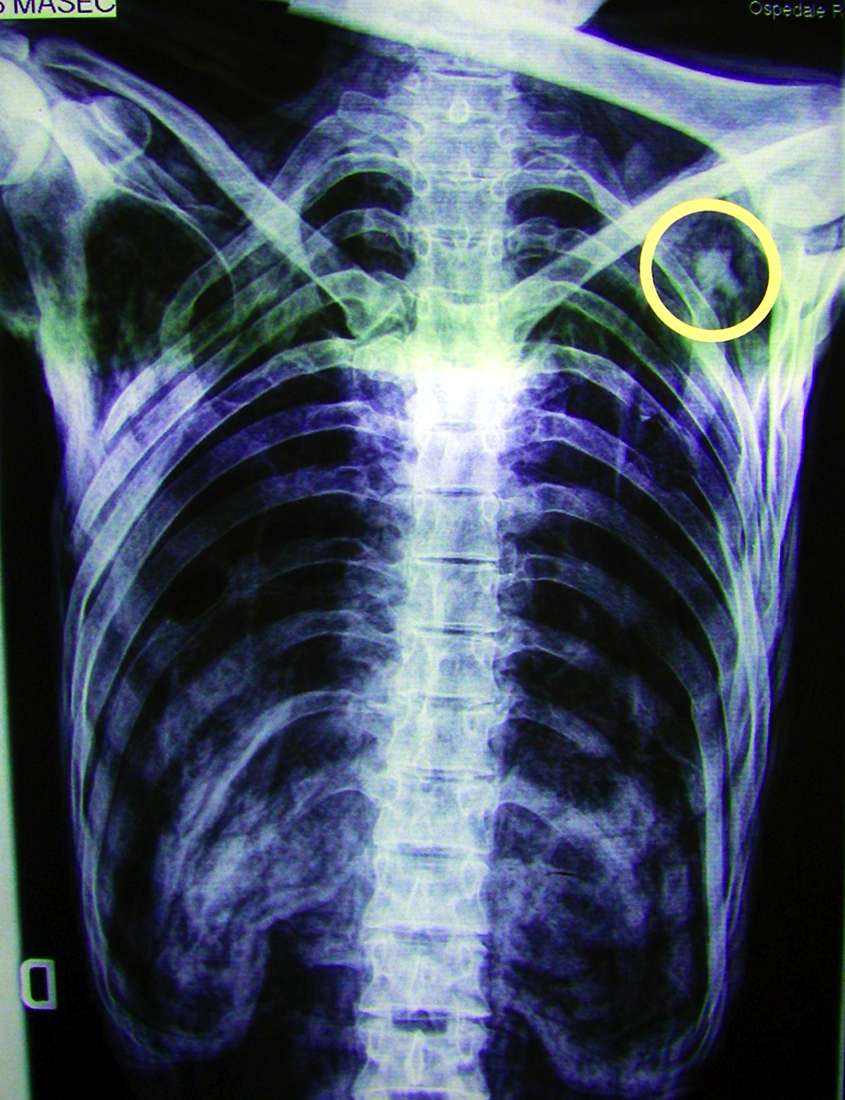

Η θεωρία αυτή ενισχύθηκε όταν, το 2001, σε νέα ακτινολογική εξέταση, εντοπίστηκε στον αριστερό ώμο του Ότζι μια μικρή αιχμή βέλους από πυριτόλιθο που δέκα χρόνια νωρίτερα είχε διαφύγει της προσοχής. Μια πιο ενδελεχής εξέταση της πλάτης του Ότζι αποκάλυψε τραύμα μήκους δύο εκατοστών, ενδεικτικό της πορείας του βέλους: ο Ότζι είχε χτυπηθεί από πίσω και χαμηλά.

Το 2005 έγινε αξονική τομογραφία στον Ότζι, η οποία έριξε φως στο θέμα του τραύματος από το βέλος. Η αιχμή του είχε προξενήσει σκίσιμο μήκους ενός εκατοστού στην αριστερή υποκλείδια αρτηρία, η οποία μεταφέρει φρέσκο οξυγονωμένο αίμα από την καρδιά στον αριστερό βραχίονα. Το σοβαρό αυτό τραύμα θα πρέπει να προκάλεσε ακατάσχετη εσωτερική αιμορραγία και, σύντομα, τον θάνατο – πιθανώς σε διάστημα δύο λεπτών. Αλλά η αξονική έδειξε και κάτι ακόμη: υπήρξε σοβαρή αιμορραγία στη βάση του εγκεφάλου, στο σημείο που αντιστοιχούσε με το βαθούλωμα στο κρανίο του Ότζι. Την ώρα του θανάτου, υπέστη, λοιπόν, και έναν σοβαρὀ τραυματισμό στο κεφάλι. Αφού πλέον είχε επιβεβαιωθεί ότι ο θάνατος προήλθε από δολοφονική πράξη, το βασικό ερώτημα αφορούσε τις συνθήκες υπό τις οποίες συνέβη αυτό.